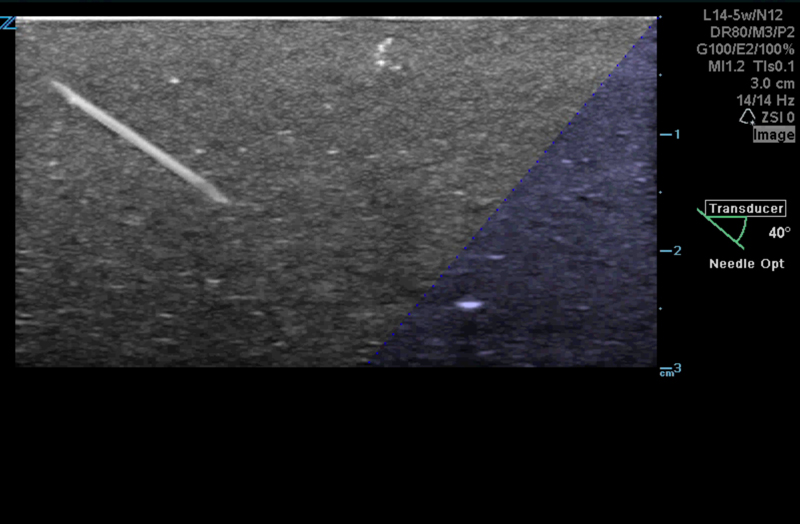

Needle Optimization

Advanced needle visualization technology allows increased needle visibility even during steep-angled procedures, while maintaining superior image quality. Improved confirmation of needle location in tissue minimizes harm to surrounding tissue.